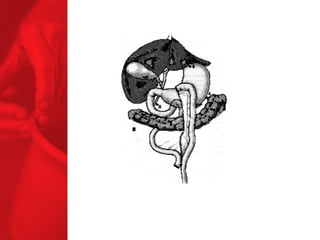

ANNEAU GASTRIQUE AJUSTABLE Procédure restrictive SAGB ®  (anneau gastrique ajustable suédois) forme d'un sablier l'opération inverse peut être effectuée la digestion et l'absorption sont normales, aucun effets secondaires de la malabsorption moyenne de surcharge pondérale à 3, 4 et 5 ans après l'étude :   49, 55 et 57% respectivement* diminue le diabète de type 2 chez près de 77% des patients** *Laparoscopic SAGB: a 5-year Prospective Study,  R. Steffen et al, Obesity Surgery, 13, 2003, 404-411 **Buchwald H, Avidor Y, Braunwald E, et al. Bariatric Surgery—A Systematic Review of the Literature and Meta-analysis. Journal of the American Medical Association 2004 Oct 13;292(14).

ANNEAU GASTRIQUE AJUSTABLEProcédure restrictive SAGB ® (anneau gastrique ajustable suédois) forme d'un sablier l'opération inverse peut être effectuée la digestion et l'absorption sont normales, aucun effets secondaires de la malabsorption moyenne de surcharge pondérale à 3, 4 et 5 ans après l'étude : 49, 55 et 57% respectivement* diminue le diabète de type 2 chez près de 77% des patients** *Laparoscopic SAGB: a 5-year Prospective Study, R. Steffen et al, Obesity Surgery, 13, 2003, 404-411 **Buchwald H, Avidor Y, Braunwald E, et al. Bariatric Surgery—A Systematic Review of the Literature and Meta-analysis. Journal of the American Medical Association 2004 Oct 13;292(14).